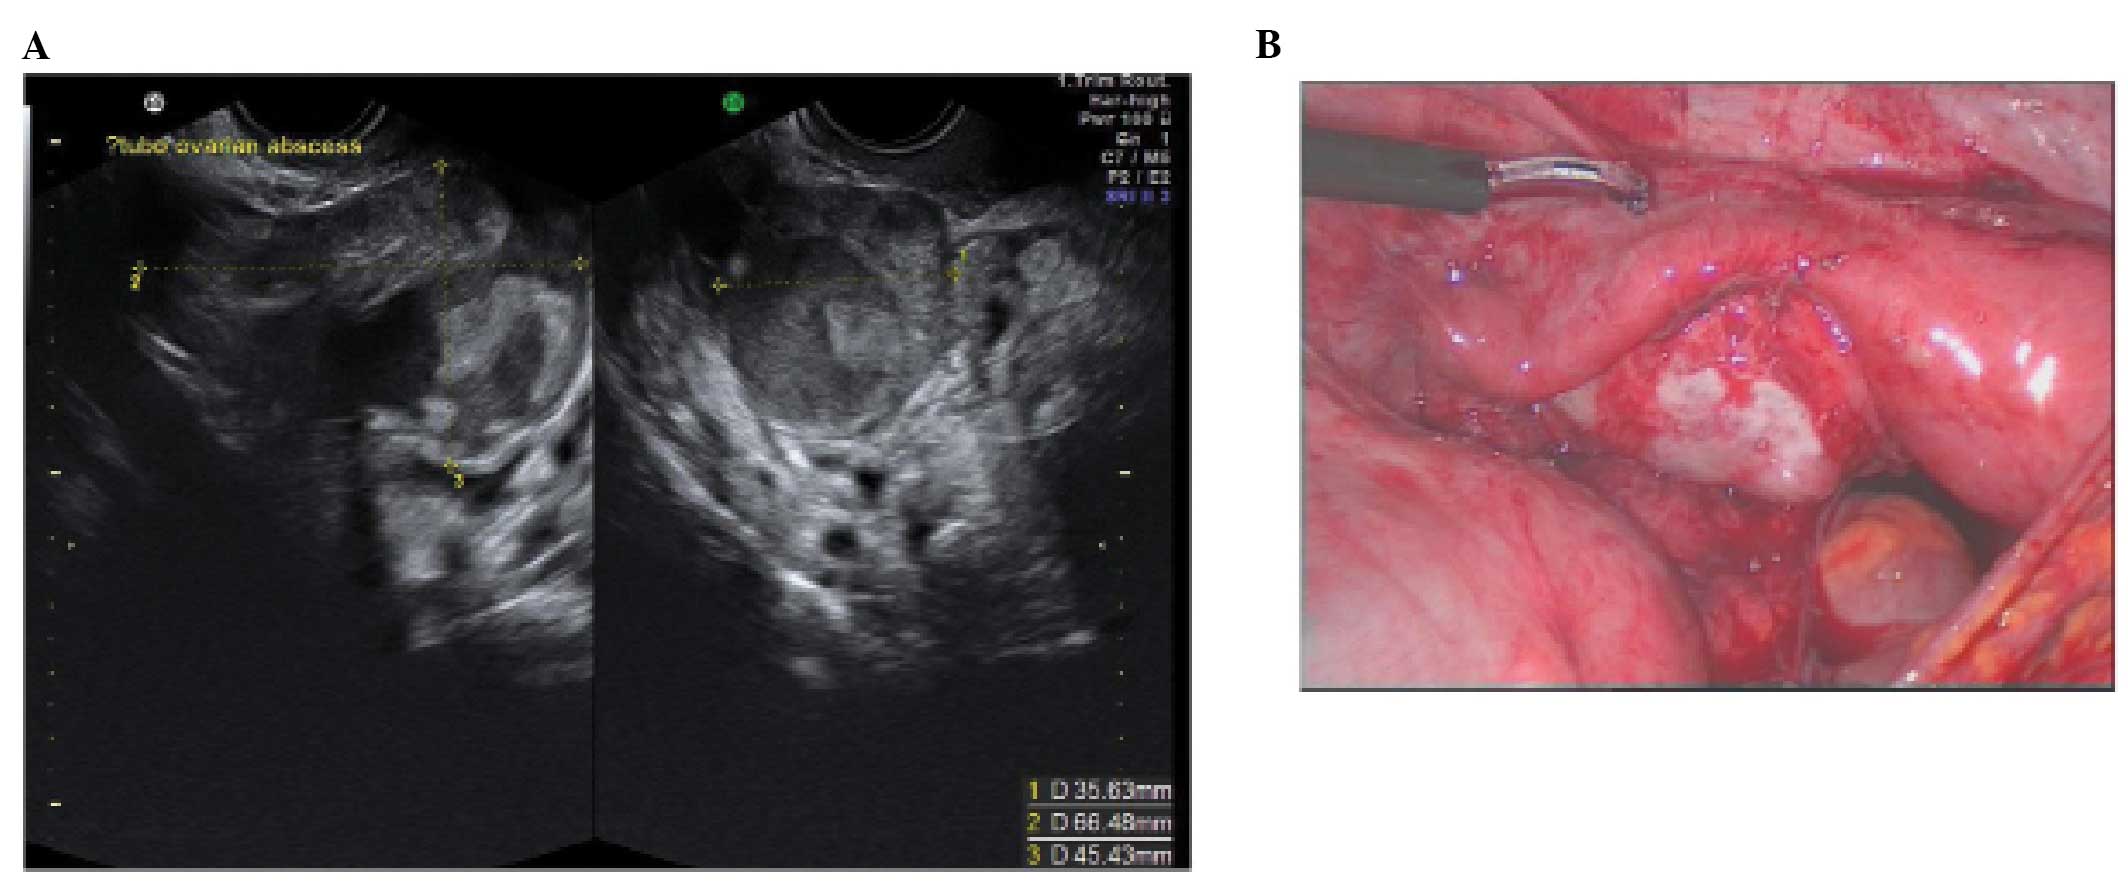

A tubo-ovarian complex represents the involvement of ovarian tissue in the inflammatory process. Normal ovarian parenchyma is visible, but it is usually seen separate from tubal structures (15,22–24) (Fig. 9).

Figure 9

A tubo-ovarian complex. (A) Ultrasound appearances. (B) The same case at laparoscopy.

In a tubo-ovarian abscess, ovarian tissue is no longer visible; the lesion may be unilocular, solid or multilocular-solid with mixed or ground-glass echogenicity. On the basis of the ultrasound features, these have to be differentiated from endometriomas or hemorrhagic cysts (15,22–24). In practice the clinical features associated with an abscess make the diagnosis relatively straightforward.